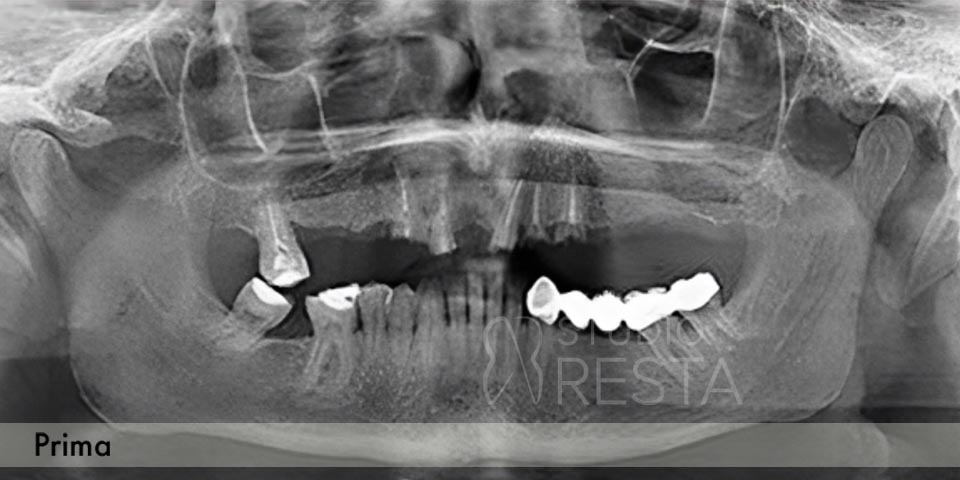

Alcuni casi clinici risolti con l'Implantologia (prima e dopo)

Vedremo le tue vecchie radiografie o te ne faremo delle nuove. Eseguiamo direttamente in studio le radiografie OPT (panoramiche) e/o la Tac Cone Beam 3D